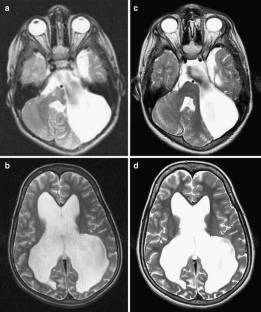

Fig. 2